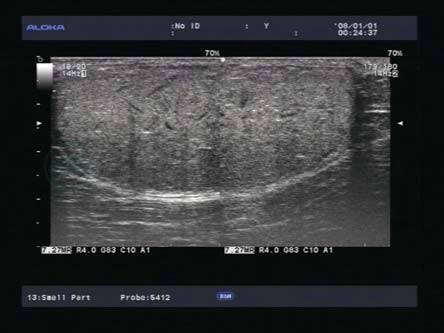

4.灰阶超声(图8-2)

(1)与皮下软组织或者肌层内长轴、或与皮肤平行。

(2)回声可为高回声、等回声或低回声。

图8-2 左侧胸壁皮下脂肪层内高回声肿块

(3)椭圆形、梭形或分叶形,绝大多数境界清楚。

(4)内部见条索状、带状高回声,与皮肤平行,呈典型的“条纹”或“羽毛状”。

(5)后方回声无明显改变。

(6)表浅者可压缩变形。

5.彩色多普勒 大多数瘤体内部无血流信号显示,偶尔扫及少许点、线状血流信号。